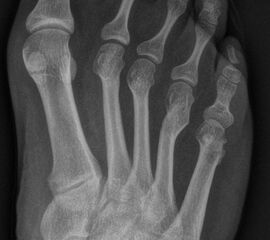

In der Regel bestehen aktive Wachstumsfugen bei Mädchen bis zum 12. und bei Jungen bis zum 14. Lebensjahr, mit Abweichungen von einem Jahr nach unten und nach oben. Präzise Informationen unter anderem darüber gibt das präoperative Röntgenbild (Abb. 2).

Abb. 2 a-c: offene Wachstumsfugen MT I Basis und Zehen (a), teilweise geöffnete Wachstumsfugen (b) und geschlossene Wachstumsfugen (c).

Zum Lesen der Bildbeschreibung und zur Vollansicht bitte die Bilder anklicken. Bilder: A. Helmers.